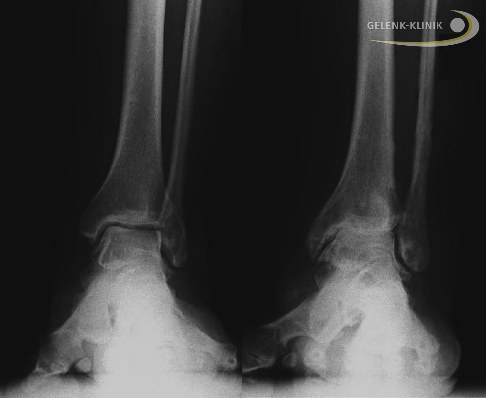

Üblicherweise werden vor der Behandlung mit einem Distraktionsfixateur verschiedene technische Untersuchungen notwendig. Belastete radiologische Untersuchungen helfen nicht nur bei der Analyse der Schädigung und der Therapieentscheidung. Sie ermöglichen auch, weitere Fehlstellungen zu erkennen, die vor einer Distraktionsarthroplastik begradigt werden sollten.

- Heute wird dafür vor allem die Digitale Volumentomographie (DVT) herangezogen. Durch sie ist eine dreidimensionale Darstellung von Knochenanbauten (Osteophyten und, Knochenzysten (durch Überdruck im Rahmen der Arthrose entstandene Hohlräume) unterhalb des Knorpels sowie von Fehlstellungen im Gelenk möglich. Weiterhin können die subchondralen (unter dem Knorpel liegenden) Knochenveränderungen wie Sklerosierung (Verdichtung) der Knochenlamelle dargestellt und beurteilt werden. Die Methode dient nicht nur zur Diagnose, sie ist auch im weiteren Verlauf der Distraktionsarthroplastik zur Überprüfung des Heilungsverlaufs nützlich.